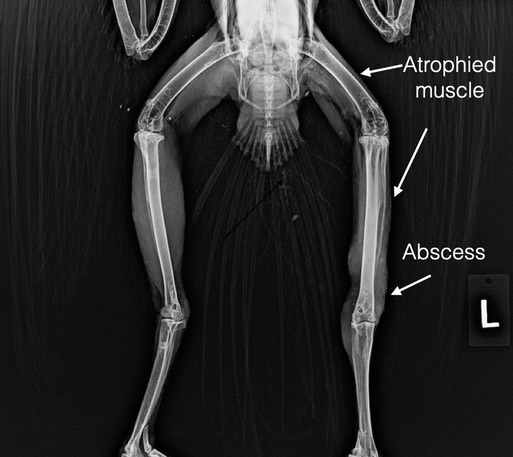

Red-tailed Hawk 22-403

This adult female Red-tailed Hawk was found on State Line Road near Milton-Freewater. She has abrasions on both legs consistent with road rash. We presume she was struck by a vehicle. She has an abscess on her left leg likely the result of bite wounds, perhaps from a rodent she was trying to capture. The road rash is recent. The bites wounds are a week or two old. She is on antibiotics and pain medication.